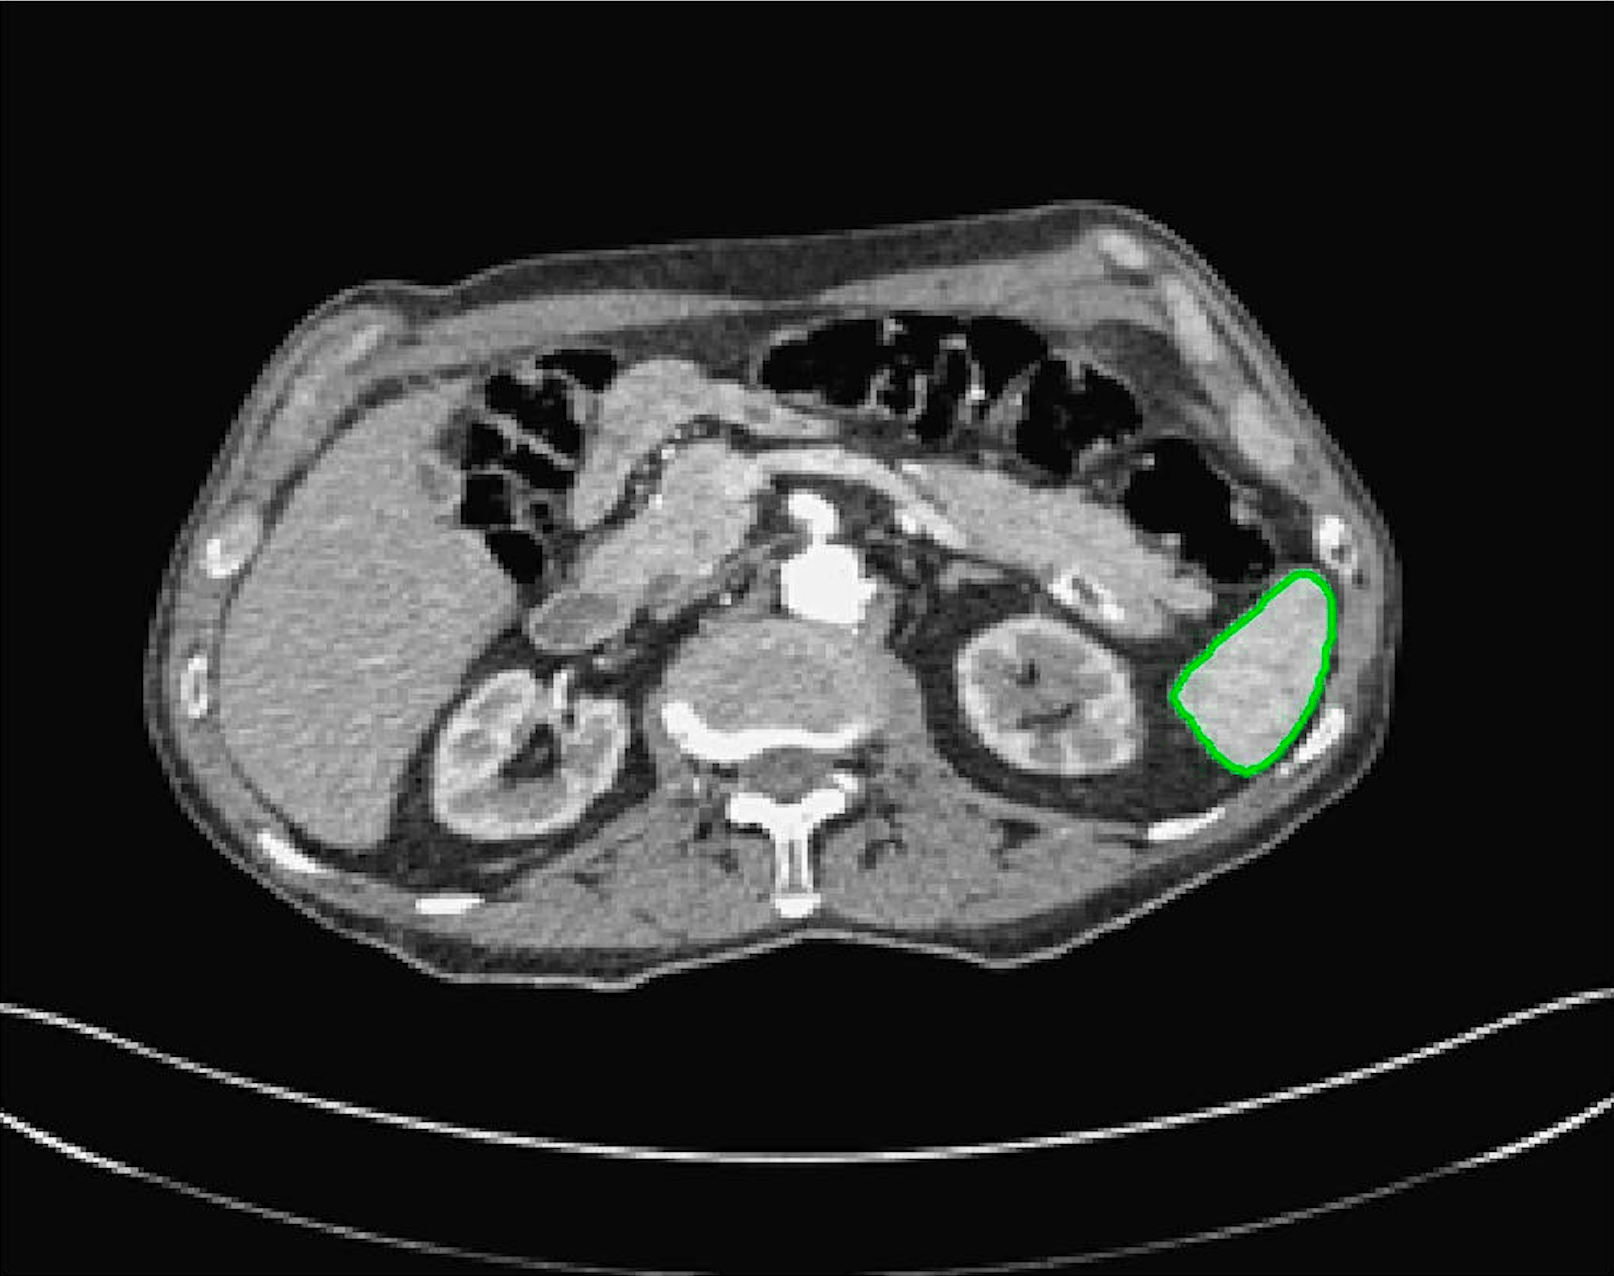

Test Images. We will perform initial tests on the images shown in Figs. 5–7. We have provided the ground truth and initialisation used for each image. Test Images 1–3 are synthetic, Test Image 4 is an MRI scan of a knee, Test Images 5–6 are abdominal CT scans, and Test Images 7–9 are lung CT scans. They have been selected to present challenges relevant to the discussion in §2. We focus on medical images as this is the application of most interest to our work. In the following we will discuss the results in terms of synthetic images (1–3) and real images (4–9). We also test the proposed approach on a larger data set of 30 CT images (a sample of which is presented in Fig. 18), comparing against existing selective methods detailed in §3.

Real Images. In Fig 12 we present results for Test Images 4–6. Here, the proposed model performs in a similar way to its competitors because these images are more typical selective segmentation problems in the sense that there is a clear distinction between the foreground and background intensities. In particular, the values in each case are: Test Image 4 , Test Image 5 , and Test Image 6 . It can be seen that the proposed model is competitive compared to previous approaches. The performance is quite poor for Test Image 5, but is arguably still the best for this challenging case. In Fig. 13 we present results for Test Images 7–9. Here the proposed model outperforms previous approaches significantly for each image. This is mainly due to the type of image considered. Specifically, the true intensities are: Test Image 7 , Test Image 8 , and Test Image 9 . The proposed model is capable of achieving results where , with other models failing completely in these cases.